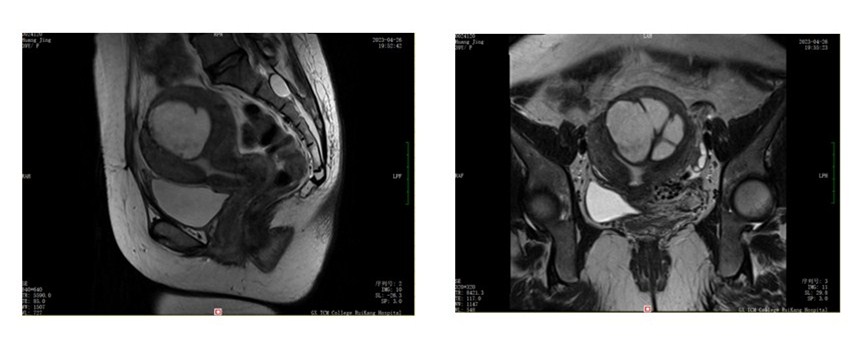

盆腔MR平扫+增强:子宫底部肌层占位,内见一类圆形短T1长T2信号影,边界清楚,内可见分隔,大小约63mmx56mmx49mm,子宫腔受压。考虑囊性子宫腺肌症。